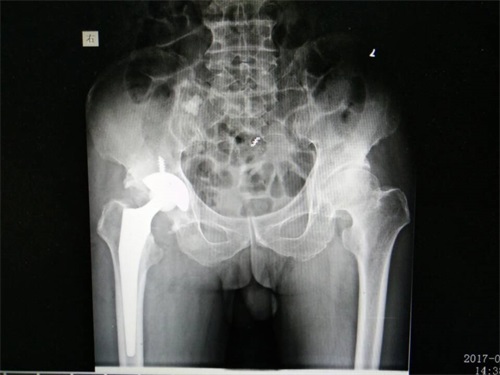

治疗方案:人工髋关节置换(全髋)术:约1个半小时的人工髋关节置换(全髋)术手术,采用改良后外侧入路,“工”型切开关节囊,将坏死的股骨头完全摘除,垂直打磨臼底,外展45度、前倾15度,安置合适的髋臼假体,安置髋臼内衬。可视操作,人工关节附近放入负压引流管,经切口外皮肤上另戳一小切口中引出皮外,清点纱布、器械无缺,然后分层缝合伤口,加压包扎。

▲图为人工髋关节置换(全髋)术后的X光片